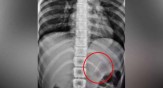

പന്ത്രണ്ടു വയസ്സുകാരി മഫ്ത്ത ധരിക്കുന്നതിനിടെ വായില് കടിച്ചു പിടിച്ച പിന് അബദ്ധത്തില് വിഴുങ്ങി... ആമാശയത്തില് കുടുങ്ങിയ പിന് സര്ജറി കൂടാതെ പുറത്തെടുത്തു

പന്ത്രണ്ടു വയസ്സുകാരി മഫ്ത്ത ധരിക്കുന്നതിനിടെ വായില് കടിച്ചു പിടിച്ച പിന് അബദ്ധത്തില് വിഴുങ്ങി... ആമാശയത്തില് കുടുങ്ങിയ പിന് സര്ജറി കൂടാതെ പുറത്തെടുത്തു. തമിഴ്നാട് ഗൂഡല്ലൂര് സ്വദേശിനിയായ 12 വയ...